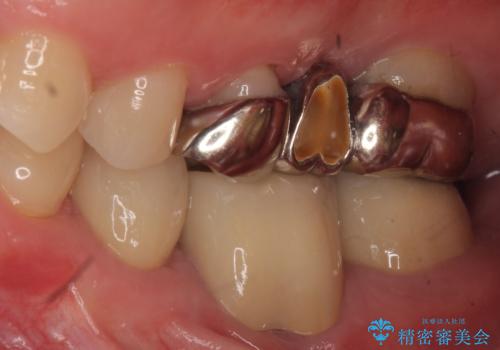

痛みの原因は6番目の虫歯であること、5番目、6番目の歯は歯茎より深い虫歯であり現状では保存が難しいことを説明した上で、歯を挺出させる部分矯正と歯茎を下げる歯周外科を行いました。

手術後歯茎の治癒を待ち、オールセラミッククラウンによる補綴を行いました。

今回用いたオールセラミッククラウンはジルコニアフレームという白い素材の上にセラミックを盛っているため、審美性が非常に高いのが特徴です。

また、ジルコニアは人工ダイヤモンドの材料にも使われているほど高い強度を持っており、そのためオールセラミッククラウンは審美性だけでなく、奥歯やブリッジの補綴も可能とするクラウンです。